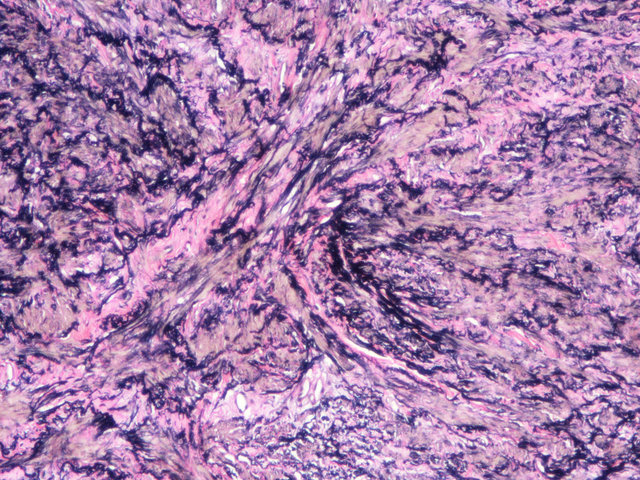

EVG染色样片参考:

EVG-VG复染

EVG染色实验结果:

弹性纤维呈蓝黑色;胶原纤维呈红色;背景呈淡黄色。